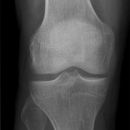

Rosenbergaufnahme

Die normale Gelenkspaltweite beträgt medial etwa 4 und lateral etwa 5 mm. Bei einer Gelenkspaltverschmälerung auf 2mm oder weniger muss von einem fortgeschrittenen, großflächigen Knorpelschaden in dem betroffenen Kompartment im Sinne einer manifesten Arthrose ausgegangen werden.

Beurteilungskriterien

• Nachweis von Osteophyten (Randzacken)

• subchondrale Sklerosierung

• Gelenkspaltverschmälerung